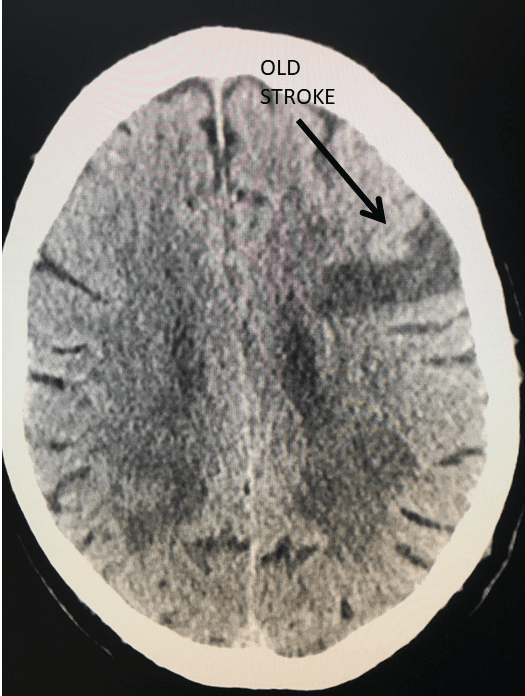

His MRI lumbar spine showed a herniated disc at L2/L3 and a grade 1 spondylolisthesis at L4/L5. Both of these findings were contributing to the patients back and leg pain.

Image 1A shows central stenosis at L4/L5 level associated with grade 1 spondylolisthesis.

Image 1B shows disc herniation at L2/L3.